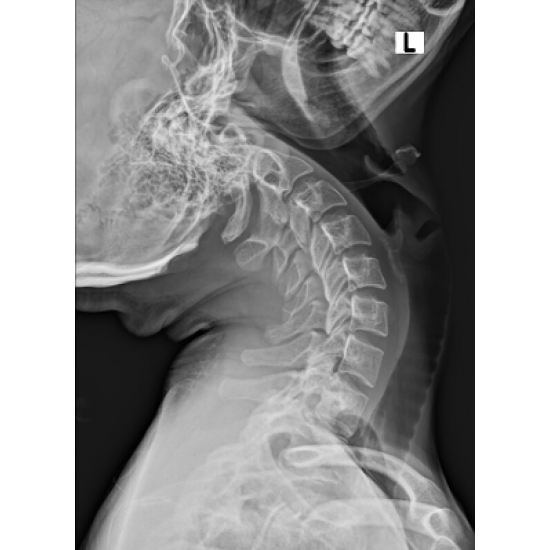

XR 4+ view cervical spine: Normal vertebral body and disc height. No acute osseous abnormality. Case Photo #1 , Case Photo #2 , Case Photo #3 , Case Photo #4